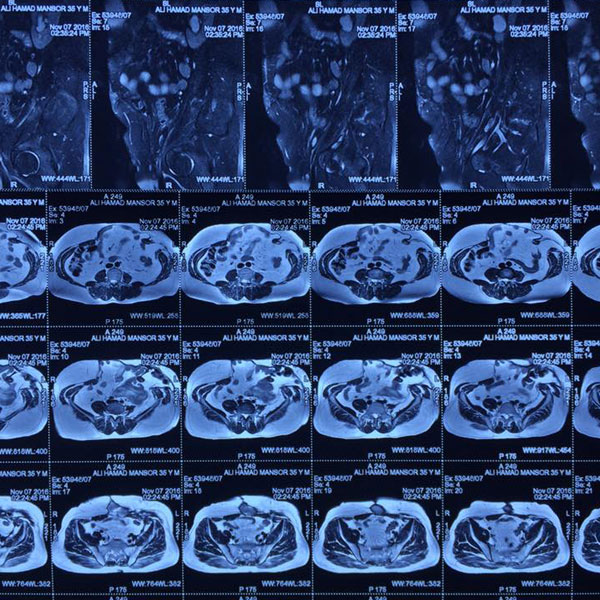

42 yr old male came with history of multiple surgeries for gun shot injury following which he devolved enterocutaneous fistula discharging faecal matter , CECT abdomen done and MR fistulogram showed midline and left iliac fossa hernia with fistula communicating with descending colon , patient undewent diagnostic laparoscopy with exploratory laparotomy with colonic and small bowel resection with both hernia repair , it was a tedious job patient was given parenteral nutrition and was discharged on the 5 post operative day , thanx God and kalka ma for blessing us.